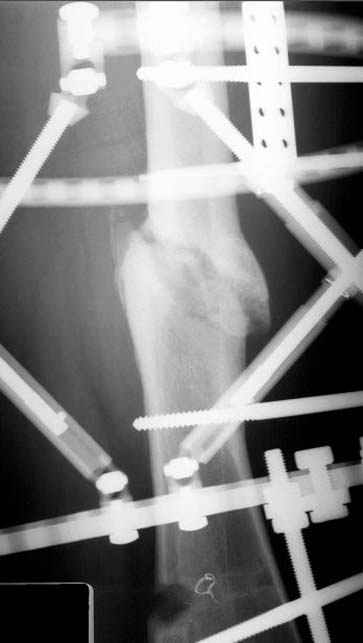

Несколько снимков из моей коллекции, чтобы разьяснить, почему мы до сих пор делаем различные варианты остеотомии.

На рисунке N1 предоперационный план лечения ложного сустава шейки бедра- линия ложного сустава, угол и направление введения импланта, клиновидная остеотомия в градусах и миллиметрах, второй снимок после коррекции, расчет, на сколько удлиняется конечность и размеры импланта;

N3 рисунок окончательный снимок, после операции моя рентгенограмма должен выглядеть примерно как эта картина. На N4 снимке клин перед удалением; N5 послеоперации 3 нед.; N6 окончательная рентгенограмма.

(доложен в Ст. Петербурге 2003 и в Москве 2004)

варус при проксимальном отделе 95 градусной пластиной.